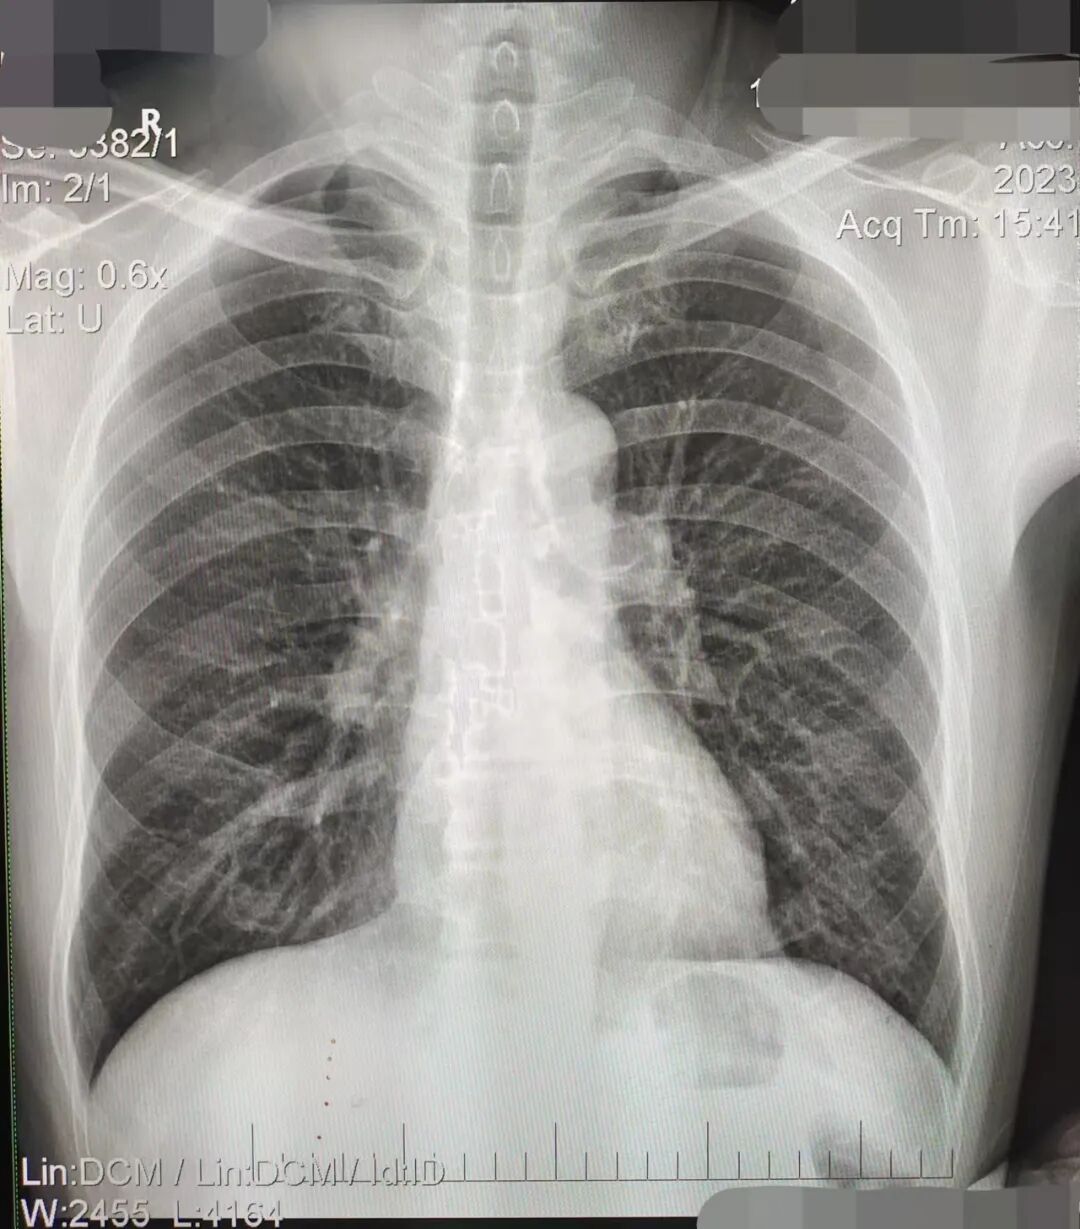

④标准影像显示部位:(1)肺尖充分显示;(2)两侧胸锁关节对称;(3)肩胛骨投影于肺野之外;(4)肺门阴影结构可辨;(5)锁骨、乳腺、左心影内可分辨出肺纹理;(6)心脏、纵膈边缘清晰锐利;(7)膈肌包括完全,且边缘锐利。如下:

DR胶片为什么分尺寸借DR成像原理详解胸部正位摄片技术参数_https://www.jmylbn.com_新闻资讯_第3张